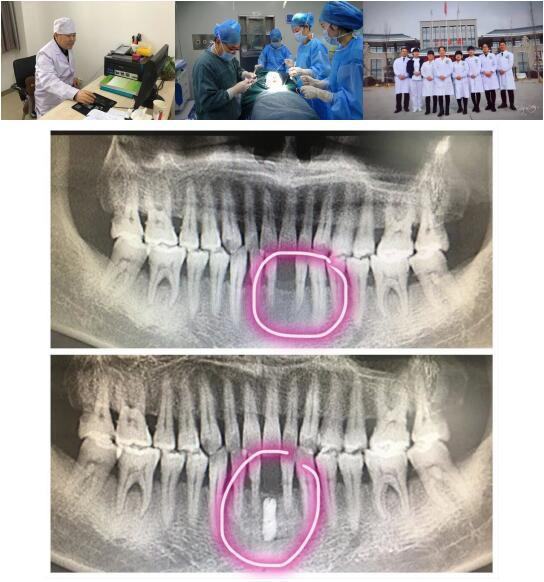

西安市第一医院高陵院区口腔科成功开展一例GBR引导骨再生技术种植牙